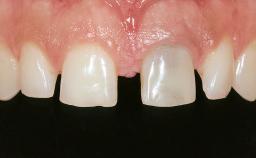

In February 2005, a 25-year-old female patient, a nonsmoker, was referred to our clinic due to tooth 11 presenting a chronic fistula following unsuccessful root-canal treatment and several attempts at endodontic surgery. The dental history revealed that more than ten years earlier, teeth 11 and 21 had been traumatized during a sports accident. Consequently, 11 had lost its vitality, and there were two moderate fractures of the mesioincisal borders of the two central incisors that had been restored with direct composite restorations. At the time of examination, the composite restorations showed signs of wear, some discoloration, and marginal infiltration. The patient also complained about a moderate discoloration of the clinical crown of the non-vital tooth 11. The patient was in good general health, and her medical history revealed no significant findings.